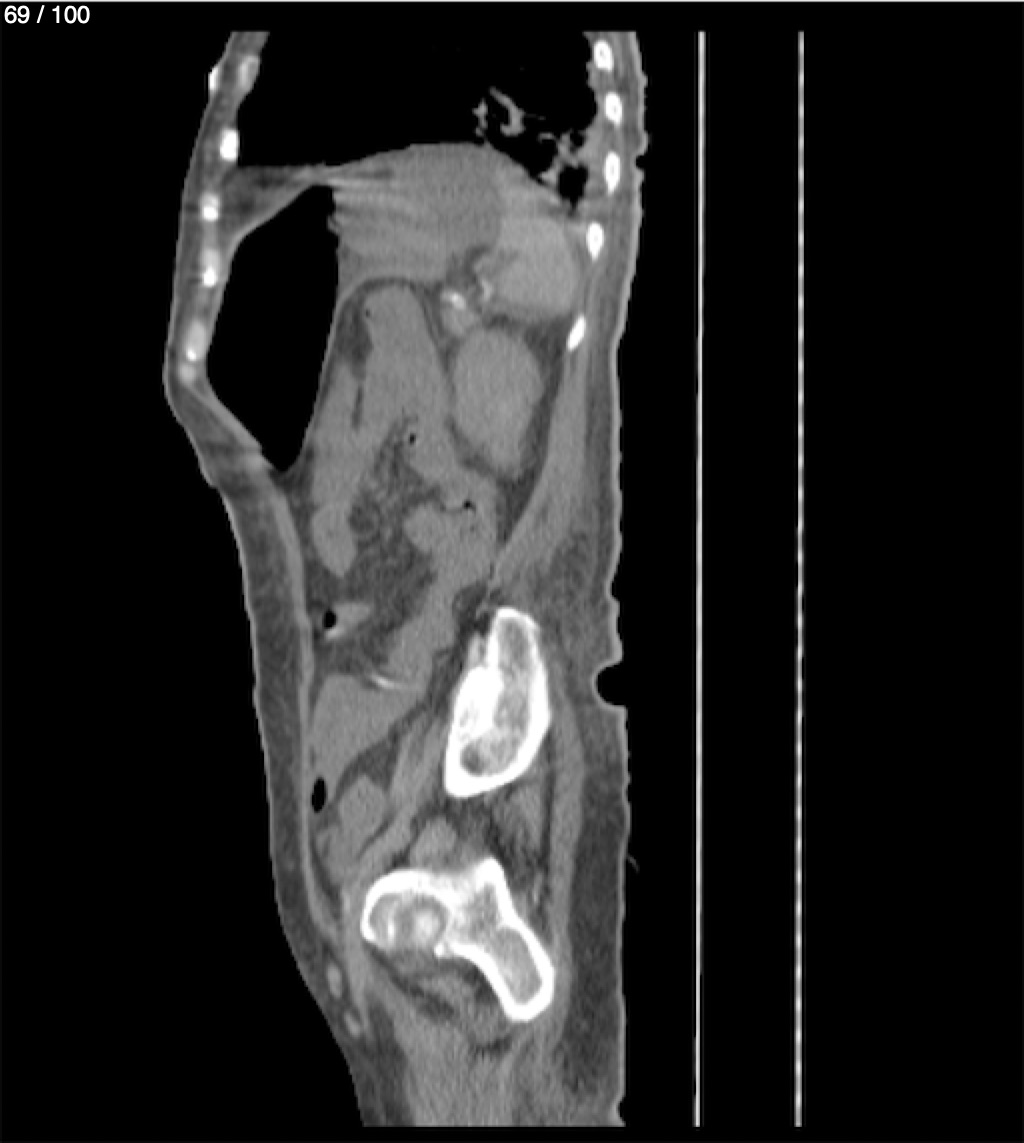

Hilda Geronimo Mendez 60A - T.C Abdomen Simple